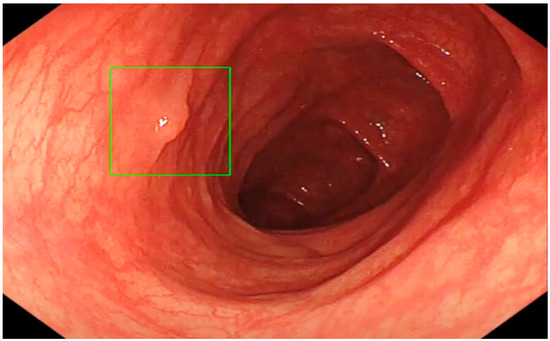

The Role of an Artificial Intelligence Method of Improving the Diagnosis of Neoplasms by Colonoscopy

2. Materials and Methods

2.4. Colonoscopy Procedure